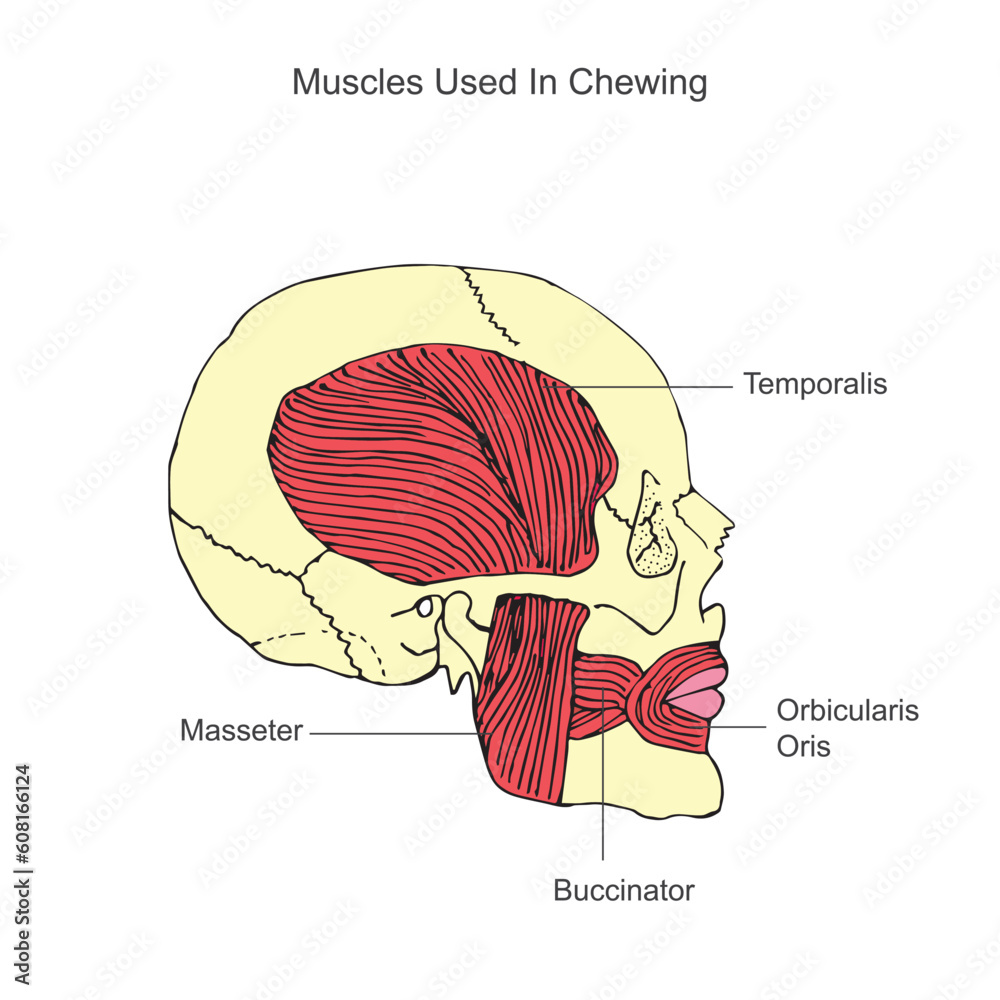

Discover the sophistication of annotated illustration of the jaw's anatomy | stable diffusion online with our curated gallery of numerous images. featuring elegant examples of photography, images, and pictures. ideal for luxury lifestyle publications. Browse our premium annotated illustration of the jaw's anatomy | stable diffusion online gallery featuring professionally curated photographs. Suitable for various applications including web design, social media, personal projects, and digital content creation All annotated illustration of the jaw's anatomy | stable diffusion online images are available in high resolution with professional-grade quality, optimized for both digital and print applications, and include comprehensive metadata for easy organization and usage. Our annotated illustration of the jaw's anatomy | stable diffusion online gallery offers diverse visual resources to bring your ideas to life. Professional licensing options accommodate both commercial and educational usage requirements. Cost-effective licensing makes professional annotated illustration of the jaw's anatomy | stable diffusion online photography accessible to all budgets. Regular updates keep the annotated illustration of the jaw's anatomy | stable diffusion online collection current with contemporary trends and styles. Multiple resolution options ensure optimal performance across different platforms and applications. Time-saving browsing features help users locate ideal annotated illustration of the jaw's anatomy | stable diffusion online images quickly. Whether for commercial projects or personal use, our annotated illustration of the jaw's anatomy | stable diffusion online collection delivers consistent excellence.